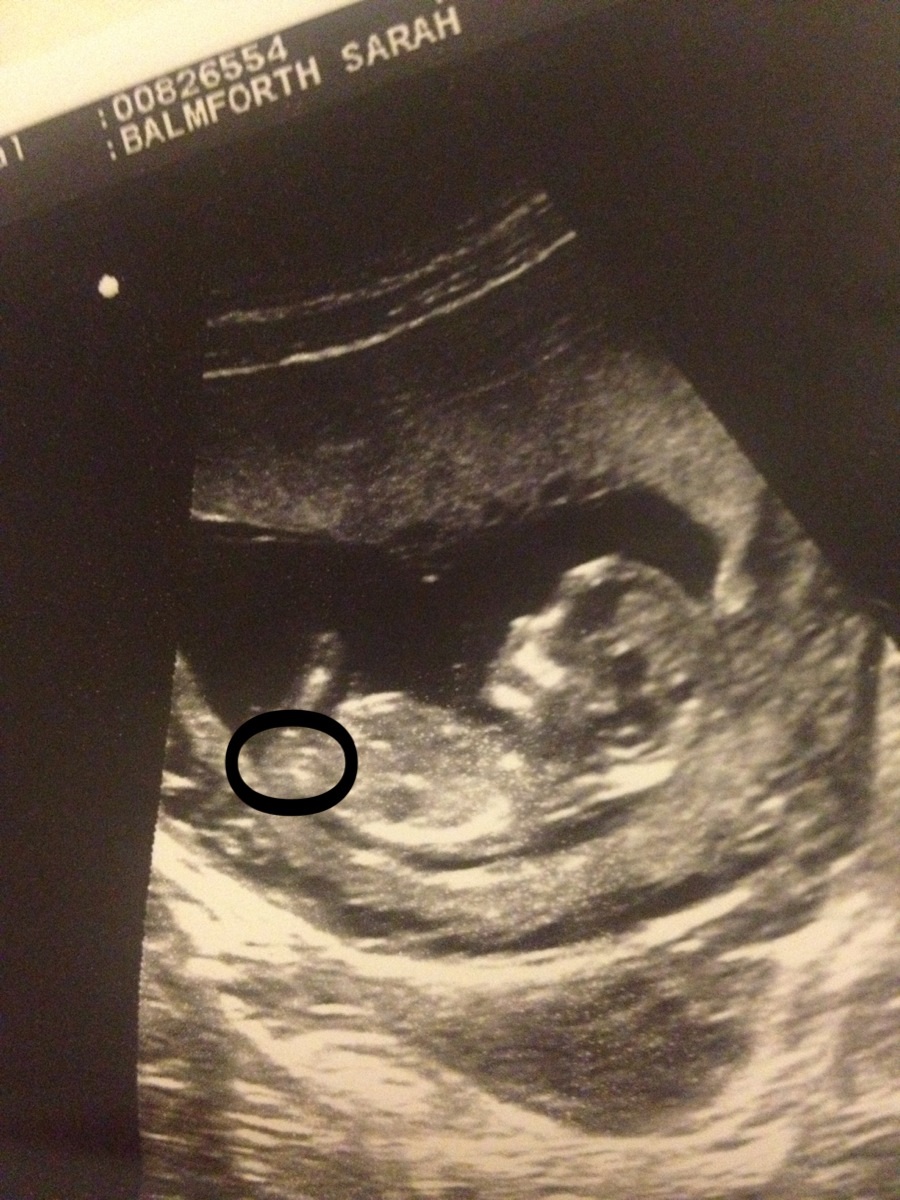

Okay after close examination i think i have found the nub, if you look within the circle there is a very dark prominent fork shape pointing --> that way above is a lighter white fork shape pointing in the opposite direction <-- is that one the nub? And if so do you think a girly or boyish nub?

Attachment 14468